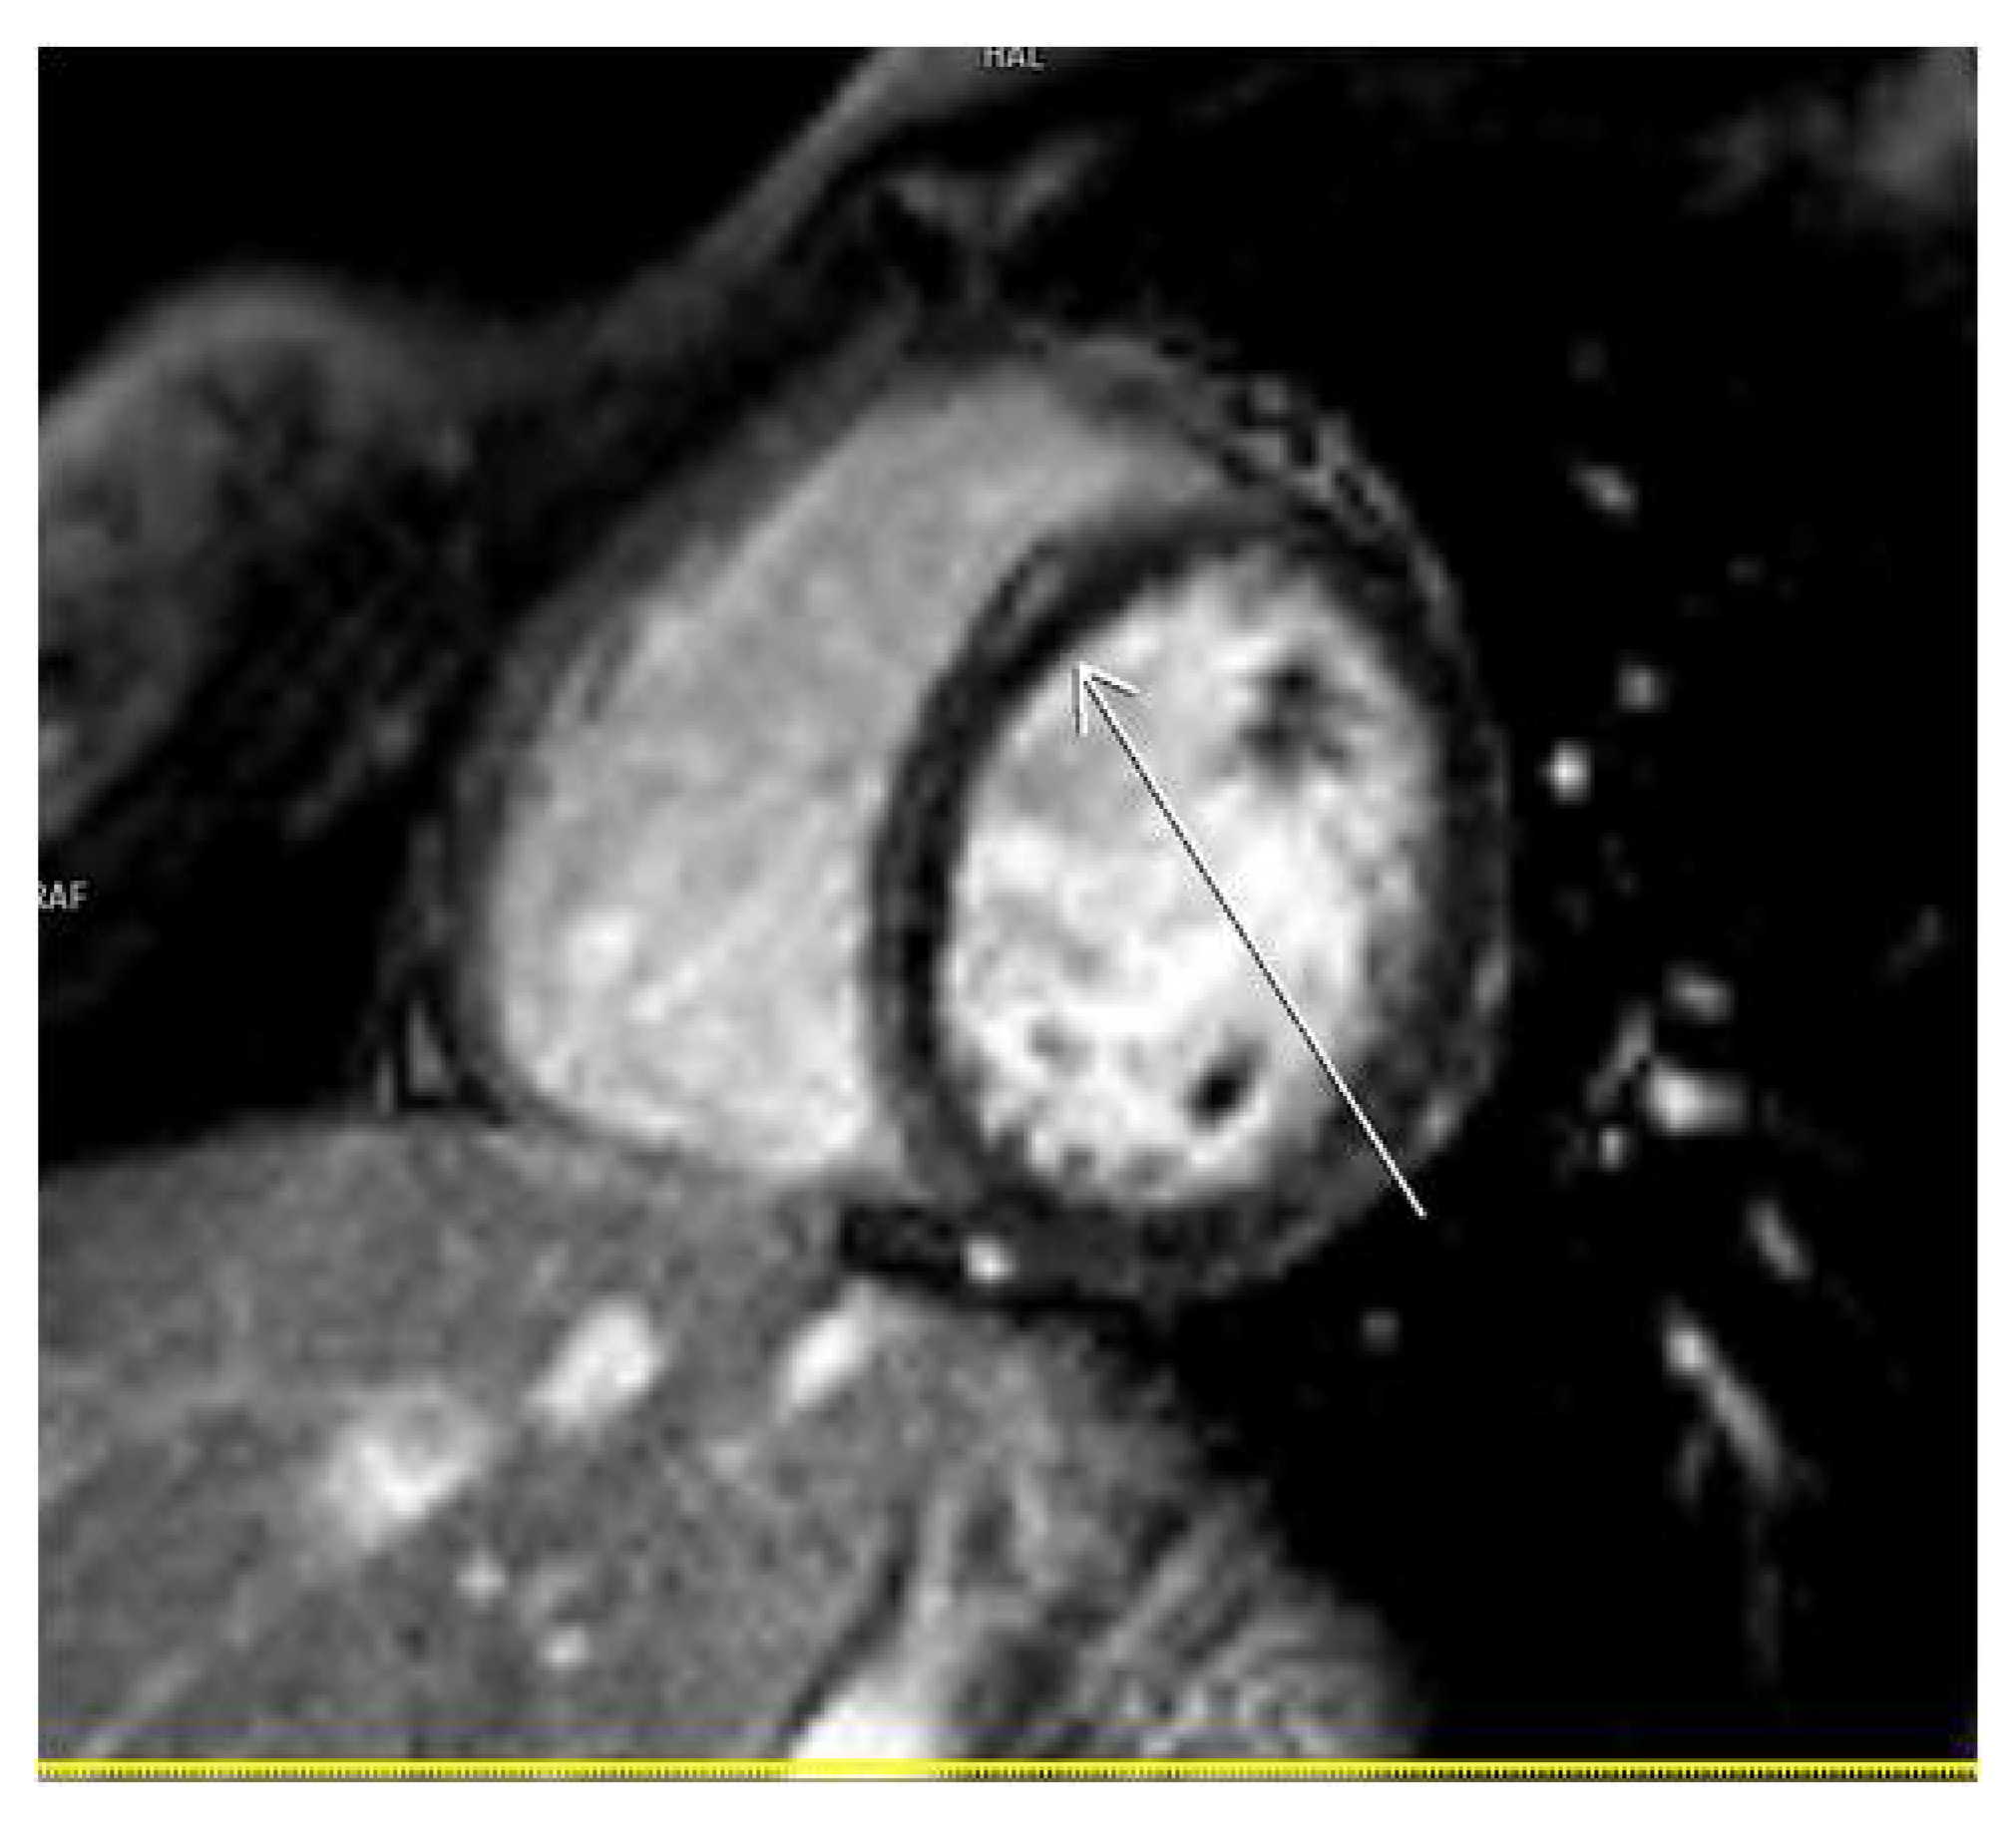

3.2. CMR Findings

3.5. LGE Localization